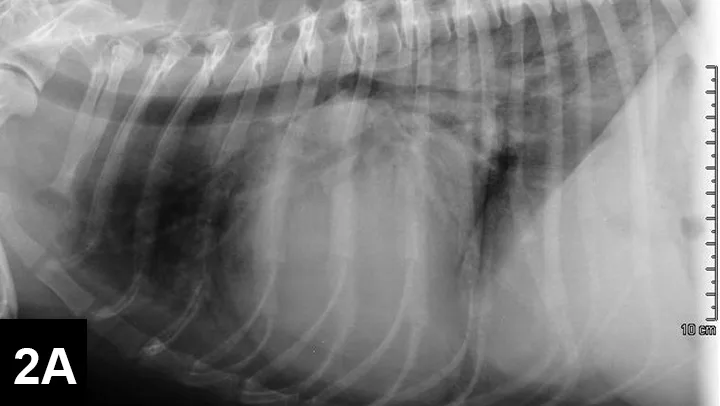

FIGURE 2A

Right lateral thoracic radiograph

A murmur and regular rhythm were auscultated. The heart rate was approximately 180 bpm, and crackles were auscultated in the caudodorsal lung fields. A 6 lead electrocardiogram (ECG, Figure 1) and thoracic radiographs (Figure 2A and 2B) were performed.

A sinus rhythm (HR is ~150 bpm) and left ventricular enlargement pattern were noted on ECG: the sensitivity was decreased to 5 mm/mV, and R waves measured ~3 mV (upper end of normal R-wave height is 2.5 mV). Thoracic radiographs revealed severe left atrial enlargement with moderate left ventricular enlargement. There was a moderate interstitial to alveolar pulmonary pattern most pronounced in the caudodorsal lung fields, which is consistent with left-sided congestive heart failure resulting from degenerative mitral valve disease.